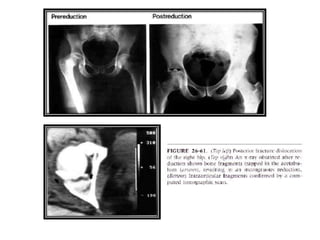

• Debe tomarse un control radiológico para comprobar la

reducción.

• La CT Scan es importante para evaluar fragmentos

osteocondrales y fracturas acetabulares.